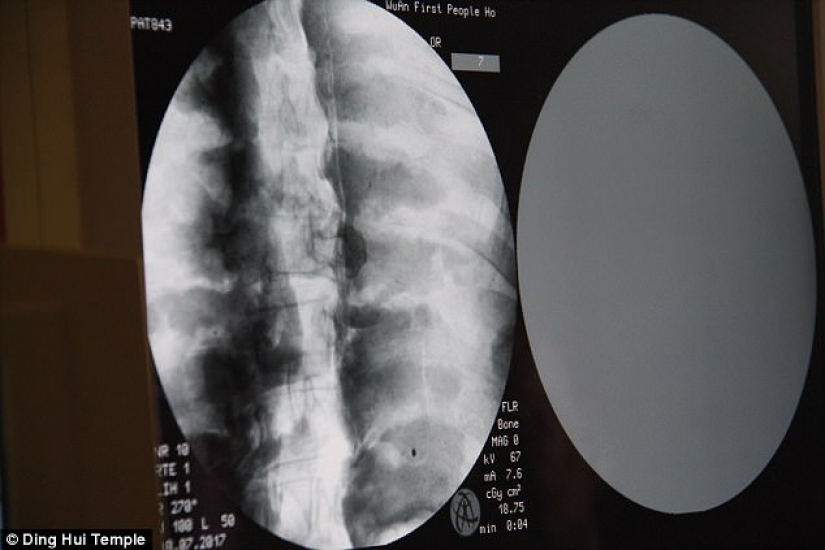

By Pictolic https://mail.pictolic.com/article/a-thousand-year-old-mummy-of-a-buddhist-monk-has-a-brain-and-skeleton-preserved-in-perfect-condition.htmlThe mummified body of a thousand-year-old Buddhist monk still has the bones and brain intact. This was revealed by a CT scan.

The CT scan was performed on July 8. People were shocked when the doctors said that Ci Xian's skeleton and brain were in perfect condition. "We can see that his bones are as healthy as a normal person's. The upper jaw, upper teeth, ribs, spine, and all joints are perfectly preserved. This is incredible, " said Dr. Wu Yongqing.